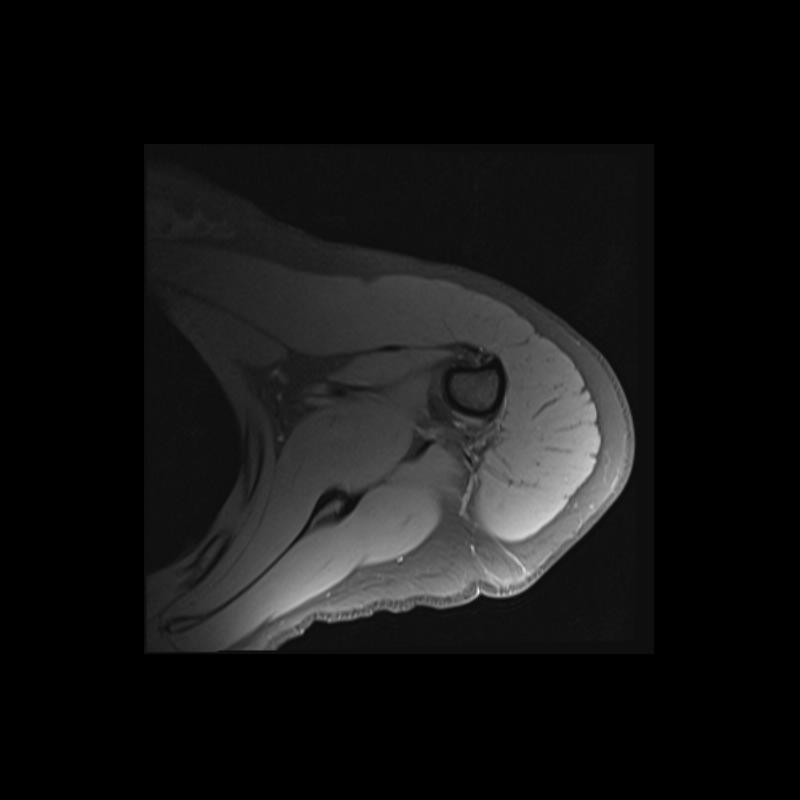

Shoulder MRI Anatomy